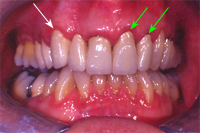

Anhand von zwei erwachsenen Patienten wollen wir den Zahnfleischrückgang bei sonst gesundem, parodontitisfreiem Zahnfleisch an überkronten Zähnen illustrieren. Da in unserer Praxis zum Zeitpunkt des Zementierens einer Krone oder Brücke der entsprechende, zirkuläre, schmale Goldrand der Krone (Abb. 7) immer etwa 1 mm unter dem Zahnfleisch verschwindet, also klinisch nicht mehr sichtbar ist (Abb. 8), kann ein im Verlaufe der Jahrzehnte resultierter Zahnfleischrückgang am Erscheinen des Goldrändchens der Metallkeramikkrone oberhalb des Zahnfleisches genau gemessen und dem Laienbetrachter optisch optimal gezeigt werden.

Im September 1983 wurde die viergliedrige Brücke auf zwei eigenen Zähnen und dem Implantat festsitzend zementiert (Kronenränder wie oben gesagt unter dem Zahnfleisch). Knapp 23 Jahre später sind bei den eigenen Pfeilerzähnen (weisse Pfeile, Abb. 10) sowie dem Implantatzahn (grüner Pfeil, Abb. 10) die Kronenränder sichtbar.

Bei einer heute 71 Jahre alten Patientin wurden in den vergangenen 22 Jahren in regelmässigen Abständen Zähne im Oberkiefer überkront (1984, 88, 96, 99). Anhand der nun klinisch sichtbaren Kronenränder (Abb. 12, 13, 14) kann die Zahnfleischrezession genau gesehen und gemessen werden. Da aber ein gesunder Zahnfleischkragen vorhanden und eine gute Mundhygiene mit regelmässiger Zahnsteinentfernung gewährleistet ist sowie die übrigen Zähne taschenfrei sind, kamen in diesem Fall nur rein prophylaktische Massnahmen zum Einsatz:

Wir sind uns auch sicher, dass die Zahnfleischrezession im Oberkiefer links (Abb. 12) zum Stillstand gekommen ist: Sie ist seit mehreren Jahren stabil. Die Tatsache, dass der Eckzahn rechts (Abb. 13, weisser Pfeil) keine Zahnfleischrezession, der mittlere und der seitliche Schneidezahn links (Abb. 13, grüne Pfeile) in der gleichen Brücke aber einen deutlichen Zahnfleischrückgang aufweisen, zeigt, dass nebst einer genetischen Komponente auch ein Zahnbürsten-traumatischer Einfluss an der Zahnfleischrezession im Oberkiefer links verantwortlich war.